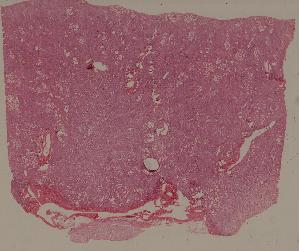

低倍视野

49. syphilitic aortitis

50. Labar pneumonia

51. Carnification of the lung

52. Lobular pneumonia

57. Carcinoma of the lung

59. Chronic atrophic gastritis

60. Gastric ulcer

61. Gastric adenocarcinoma(Mucinous adenocarcinoma of the stamoch)

62. Acute viral hepatitis (common type)

63.Chronic active viral hepatitis

64. Acute fulminant viral hepatitis

65. Subacute fulminant viral hepatitis

66. Active nodular cirrhosis of the liver

67. Inactive nodular cirrhosis of the liver

68. Biliary fibrosis

69. Hepatocellular carcinoma

72. Membranous glomerulonephritis

73. Acute glomerulonephritis

74. Crescentic glomerulonephritis

75. Chronic glomerulonephritis